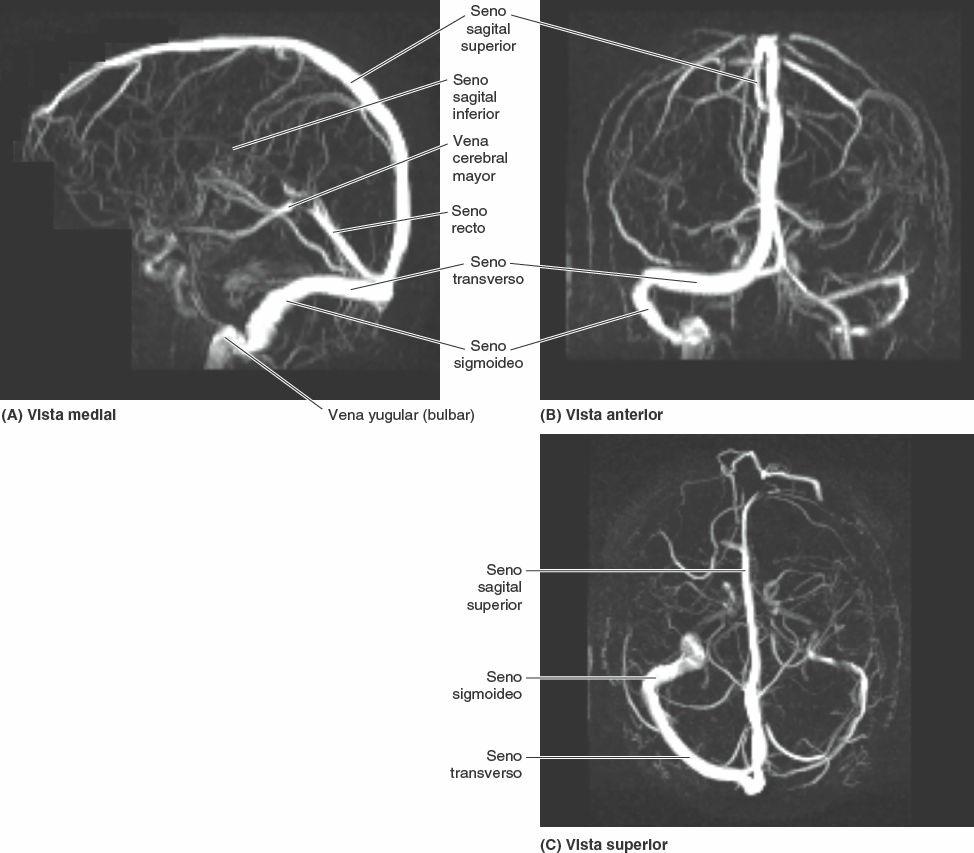

Los senos venosos de la duramadre son espacios revestidos de endotelio situados entre las capas perióstica y meníngea de la duramadre. Se forman allí donde se adhieren los septos de duramadre a lo largo del borde libre de la falce del cerebro y en relación con ciertas formaciones de la base del cráneo (figs. 8-29, 8-31 y 8-32). Las grandes venas de la superficie del encéfalo drenan en estos senos, y la mayor parte de la sangre del encéfalo drena a través de ellos en las venas yugulares internas.

El seno sagital superior se sitúa en el borde convexo de adhesión de la falce del cerebro (fig. 8-29). Se inicia en la crista galli y finaliza cerca de la protuberancia occipital interna (fig. 8-30) en la confluencia de los senos, lugar de encuentro de los senos sagital superior, recto, occipital y transversos (fig. 8-32). El seno sagital superior recibe las venas cerebrales superiores y se comunica a cada lado, a través de orificios semejantes a hendiduras, con las lagunas venosas laterales, expansiones laterales del seno sagital superior (fig. 8-29 D).

El seno sagital inferior es mucho más pequeño que el seno sagital superior (fig. 8-29). Discurre por el borde libre cóncavo inferior de la falce del cerebro y finaliza en el seno recto. El seno recto está formado por la unión del seno sagital inferior con la vena cerebral magna. Discurre inferoposteriormente a lo largo de la línea de unión de la falce del cerebro con el tentorio del cerebelo, donde se une a la confluencia de los senos.

Los senos transversos discurren lateralmente desde la confluencia de los senos y forman un surco en cada hueso occipital y los ángulos posteroinferiores de los huesos parietales (figs. 8-30 a 8-32). Los senos transversos cursan a lo largo de los bordes posterolaterales de unión del tentorio del cerebelo y luego se transforman en los senos sigmoideos cerca de la cara posterior de la porción petrosa de los huesos temporales. La sangre que llega a la confluencia de los senos drena en los senos transversos, aunque raras veces de un modo igual, pues habitualmente predomina el izquierdo (cuyo tamaño es mayor).

Los senos sigmoideos siguen un recorrido en forma de S en la fosa craneal posterior, formando profundos surcos en los huesos temporales y occipital. Cada seno sigmoideo gira anteriormente y luego continúa inferiormente como vena yugular interna después de atravesar el foramen yugular. El seno occipital se sitúa en el borde de adhesión de la falce del cerebelo y finaliza superiormente en la confluencia de los senos (fig. 8-29 B). El seno occipital comunica inferiormente con el plexo venoso vertebral interno (figs. 8-29 B y 8-33).

Los senos petrosos superiores discurren desde los extremos posteriores de las venas que componen los senos cavernosos hasta los senos transversos en el punto donde estos senos se incurvan inferiormente para formar los senos sigmoideos (fig. 8-32 B). Cada seno petroso superior está situado en el borde de adhesión anterolateral del tentorio del cerebelo, que se une al borde superior (cresta) de la porción petrosa del hueso temporal (fig. 8-30).

Los senos petrosos inferiores también comienzan en el extremo posterior de cada seno cavernoso (fig. 8-31 A y B). Cada seno petroso inferior discurre por un surco situado entre la porción petrosa del hueso temporal y la porción basilar del hueso occipital (fig. 8-30). El seno petroso inferior drena el seno cavernoso directamente en la transición del seno sigmoideo a la vena yugular interna en el foramen yugular (fig. 8-31 B). El plexo basilar conecta los senos petrosos inferiores y comunica inferior-mente con el plexo venoso vertebral interno (figs. 8-29 B y 8-33).